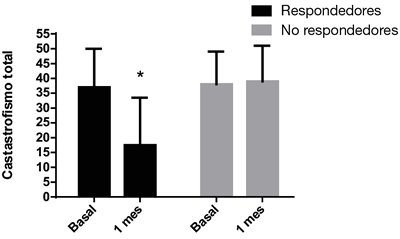

En esa población de pacientes respondedores, se observa que todos esos aspectos disminuyeron marcadamente. El EVN pasó de 8,8 ± 2,1 a 4,0 ± 3,1 con un porcentaje de cambio de 54 % (p < 0,0001), el índice de intensidad de 7,8 ± 0,8 a 3,9 ± 3,1 (50 % de porcentaje de cambio, p = 0,0001) el índice de interferencia, de 8,2 ± 1,6 a 5,0 ± 3,8 (40 % de cambio, p = 0,0027) y el catastrofismo total de 37 ± 13 a 17,5 ± 16 (57 % de cambio, p < 0,0001) (Figuras 5 y 6).

Fig. 6. Catastrofismo total, basal y al mes de la inyección epidural de esteroides en pacientes respondedores y no respondedores a las inyecciones epidurales de esteroides (p < 0,05, test de Wilcoxon).

Cuando se compara el catastrofismo total previo a la realización de las inyecciones epidurales de esteroides, se observa que el mismo no tiene diferencias significativas entre el grupo de pacientes respondedores versus los no respondedores (37 ± 13 versus 38 ± 11). Tampoco se observaron diferencias en el índice de intensidad y de interferencia basales entre ambos grupos. Los pacientes no respondedores presentaron un índice de intensidad y de interferencia basales de 7,7 ± 1 y 7,8 ± 0,8 respectivamente, mientras que los respondedores presentaron índices de intensidad y de interferencia basales de 7,5 ± 2,5 y 8,0 ± 2,1, respectivamente.